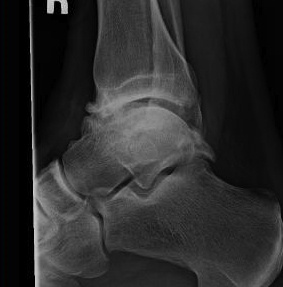

• Ankle Arthroplasty